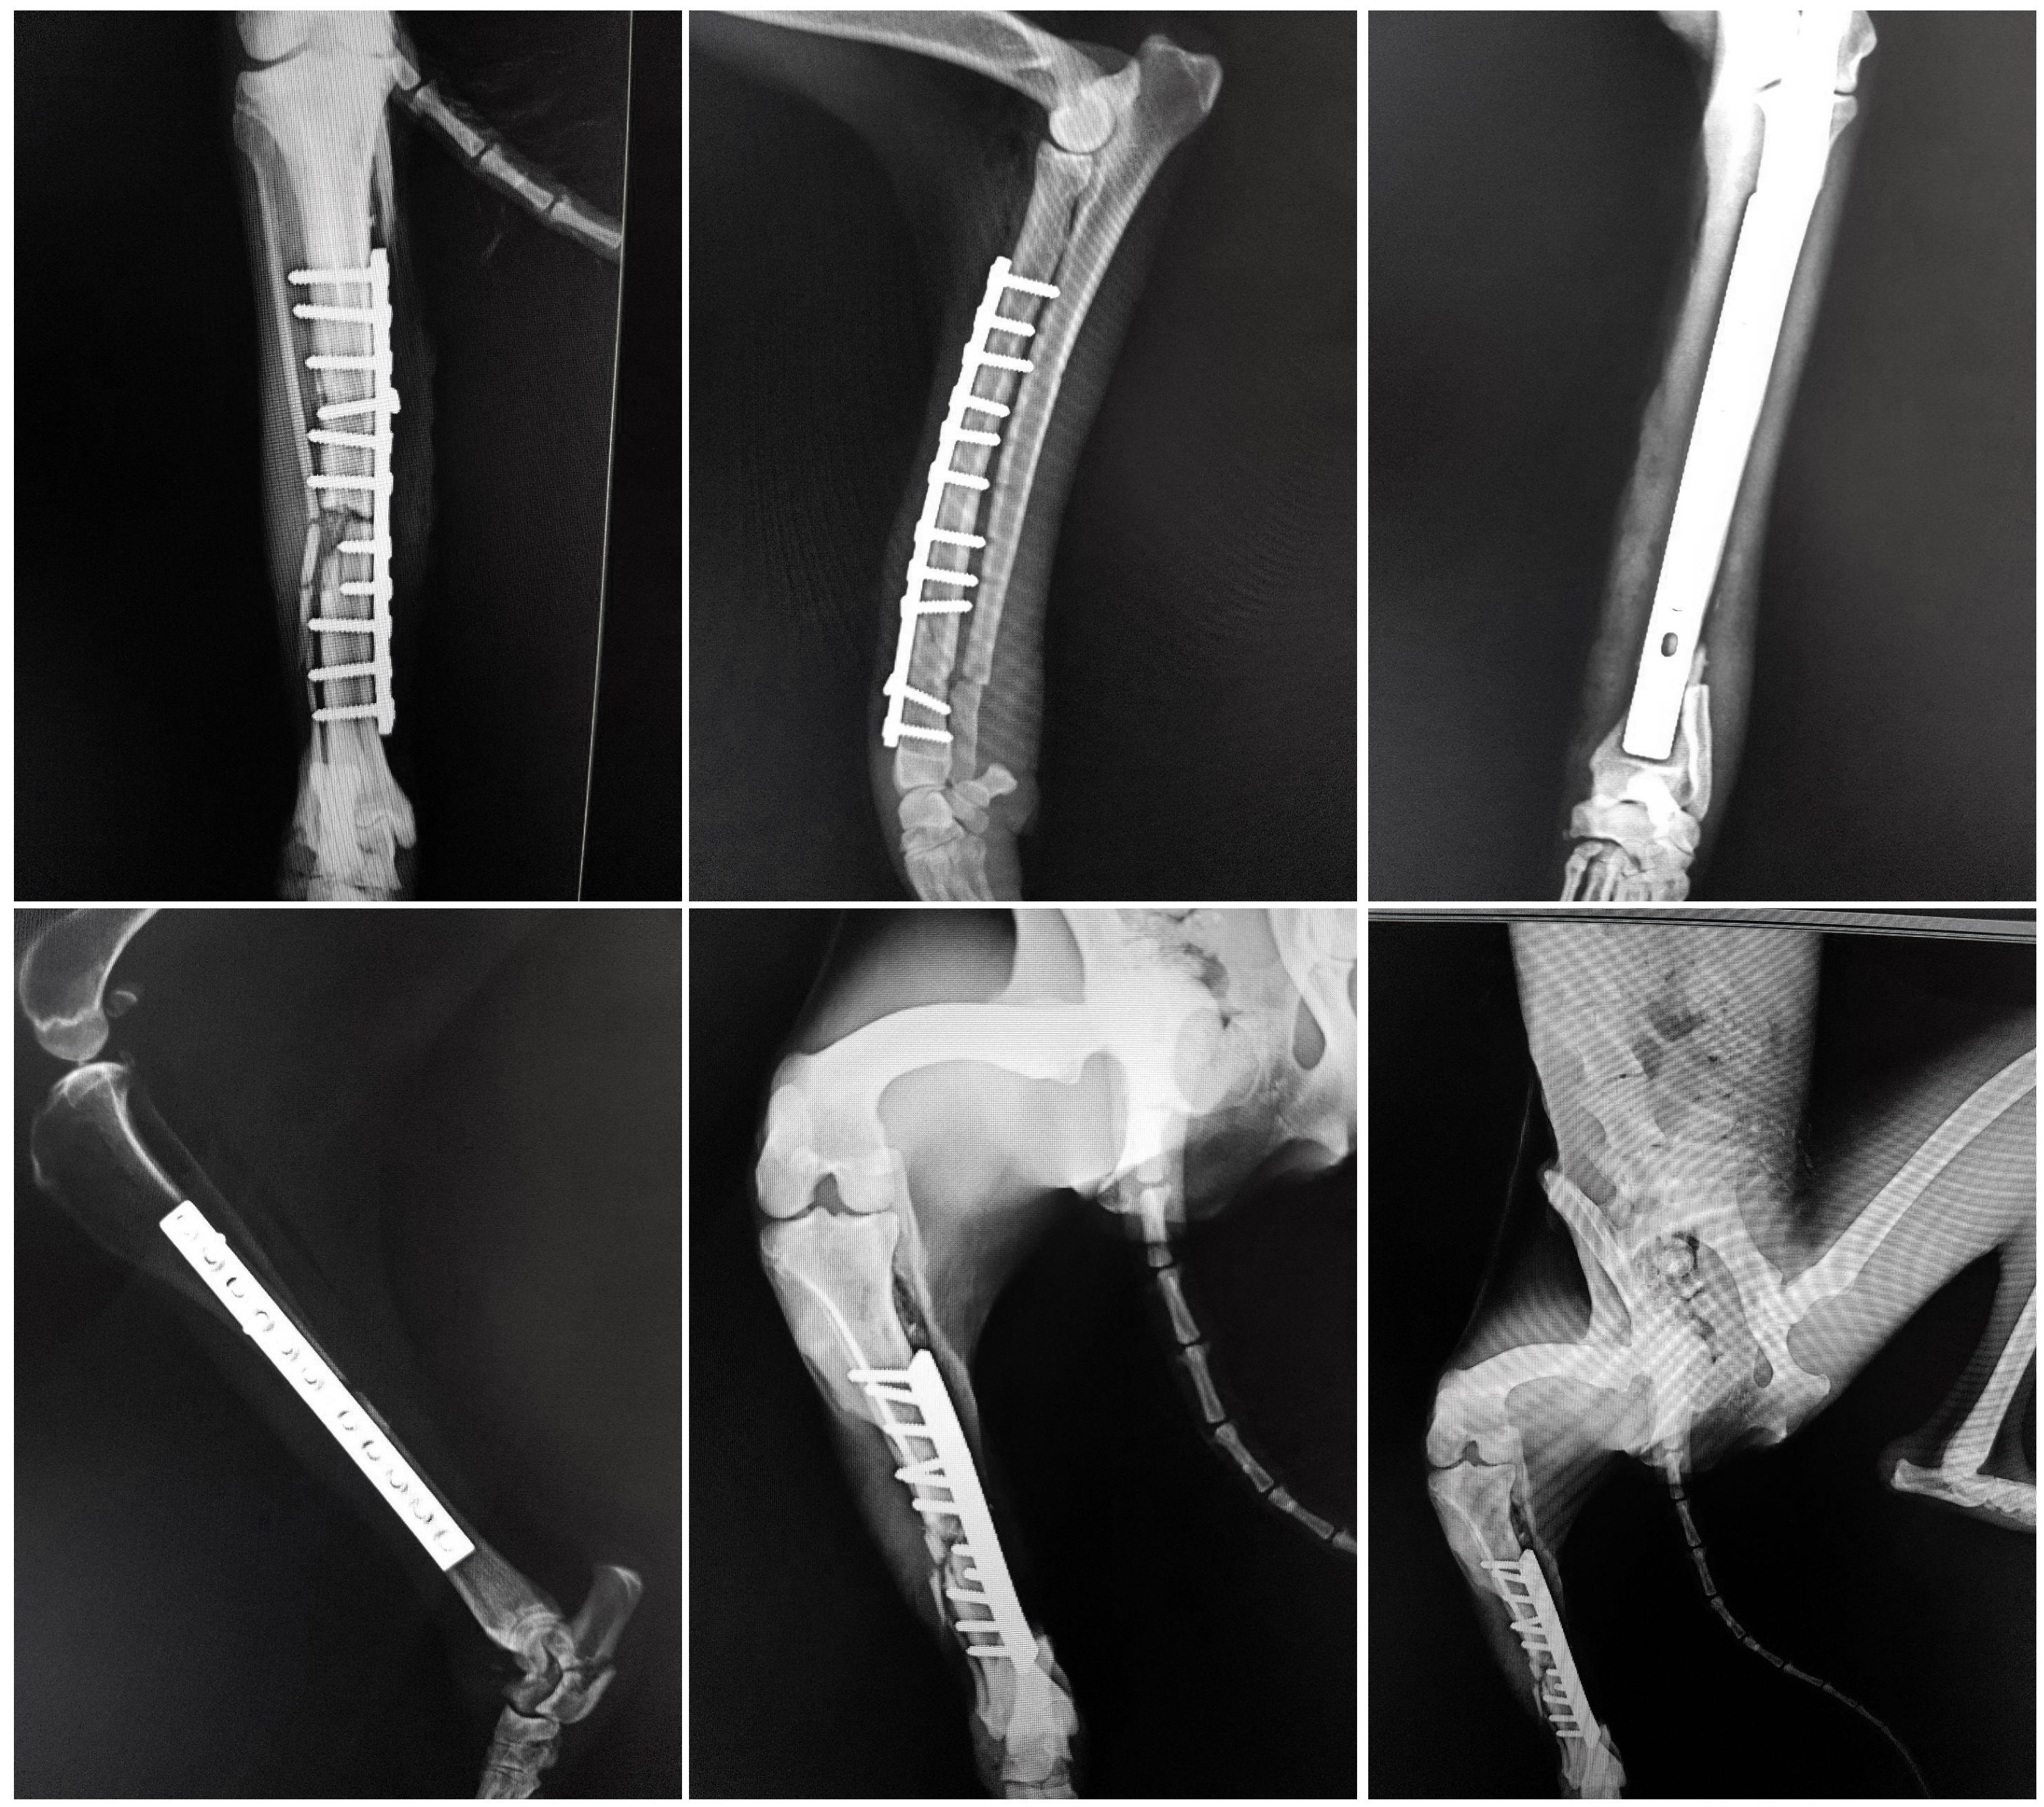

حمیدرضا فتاحیان جراح معالج شغال محمودآباد، درباره عمل جراحی این حیوان به خبرنگار اجتماعی خبرگزاری تسنیم گفت: شکستگی ساعد دست چپ این شغال ماده با استفاده از پیچ و پلیت، و شکستگی پای راست، به منظور تسریع در روند التیام شکستگی، با استفاده از پیچ و پلیت و همچنین پیوند استخوان تحت درمان جراحی قرار گرفت و در جهت کمک به روند درمان گچگیری شد. شکستگی استخوان پاشنه در مچ پای راست به دلیل وجود زخم در ناحیه مچ پای راست، مورد عمل قرار نگرفت که پس از بهبود وضعیت زخم در ناحیه مذکور و همچنین مشاهده وضعیت عمومی مناسب بیمار، در صورت نیاز به مداخله جراحی، در روزهای آتی تحت جراحی قرار خواهد گرفت.

گرفتن پیوند بافت اسفنجی از استخوان درشت نی شغال